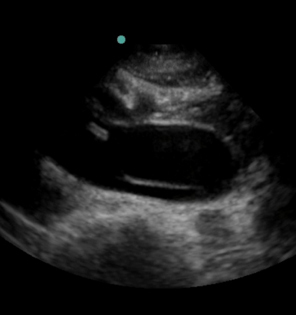

大動脈解離の横断画像